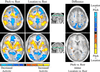

The extent to which sound identification and sound localization depend on specialized auditory pathways was examined by using functional magnetic resonance imaging and event-related brain potentials. Participants performed an S1-S2 match-to-sample task in which S1 differed from S2 in its pitch and/or location. In the pitch task, participants indicated whether S2 was lower, identical, or higher in pitch than S1. In the location task, participants were asked to localize S2 relative to S1 (i.e., leftward, same, or rightward). Relative to location, pitch processing generated greater activation in auditory cortex and the inferior frontal gyrus. Conversely, identifying the location of S2 relative to S1 generated greater activation in posterior temporal cortex, parietal cortex, and the superior frontal sulcus. Differential task-related effects on event-related brain potentials (ERPs) were seen in anterior and posterior brain regions beginning at 300 ms poststimulus and lasting for several hundred milliseconds. The converging evidence from two independent measurements of dissociable brain activity during identification and localization of identical stimuli provides strong support for specialized auditory streams in the human brain. These findings are analogous to the "what" and "where" segregation of visual information processing, and suggest that a similar functional organization exists for processing information from the auditory modality.